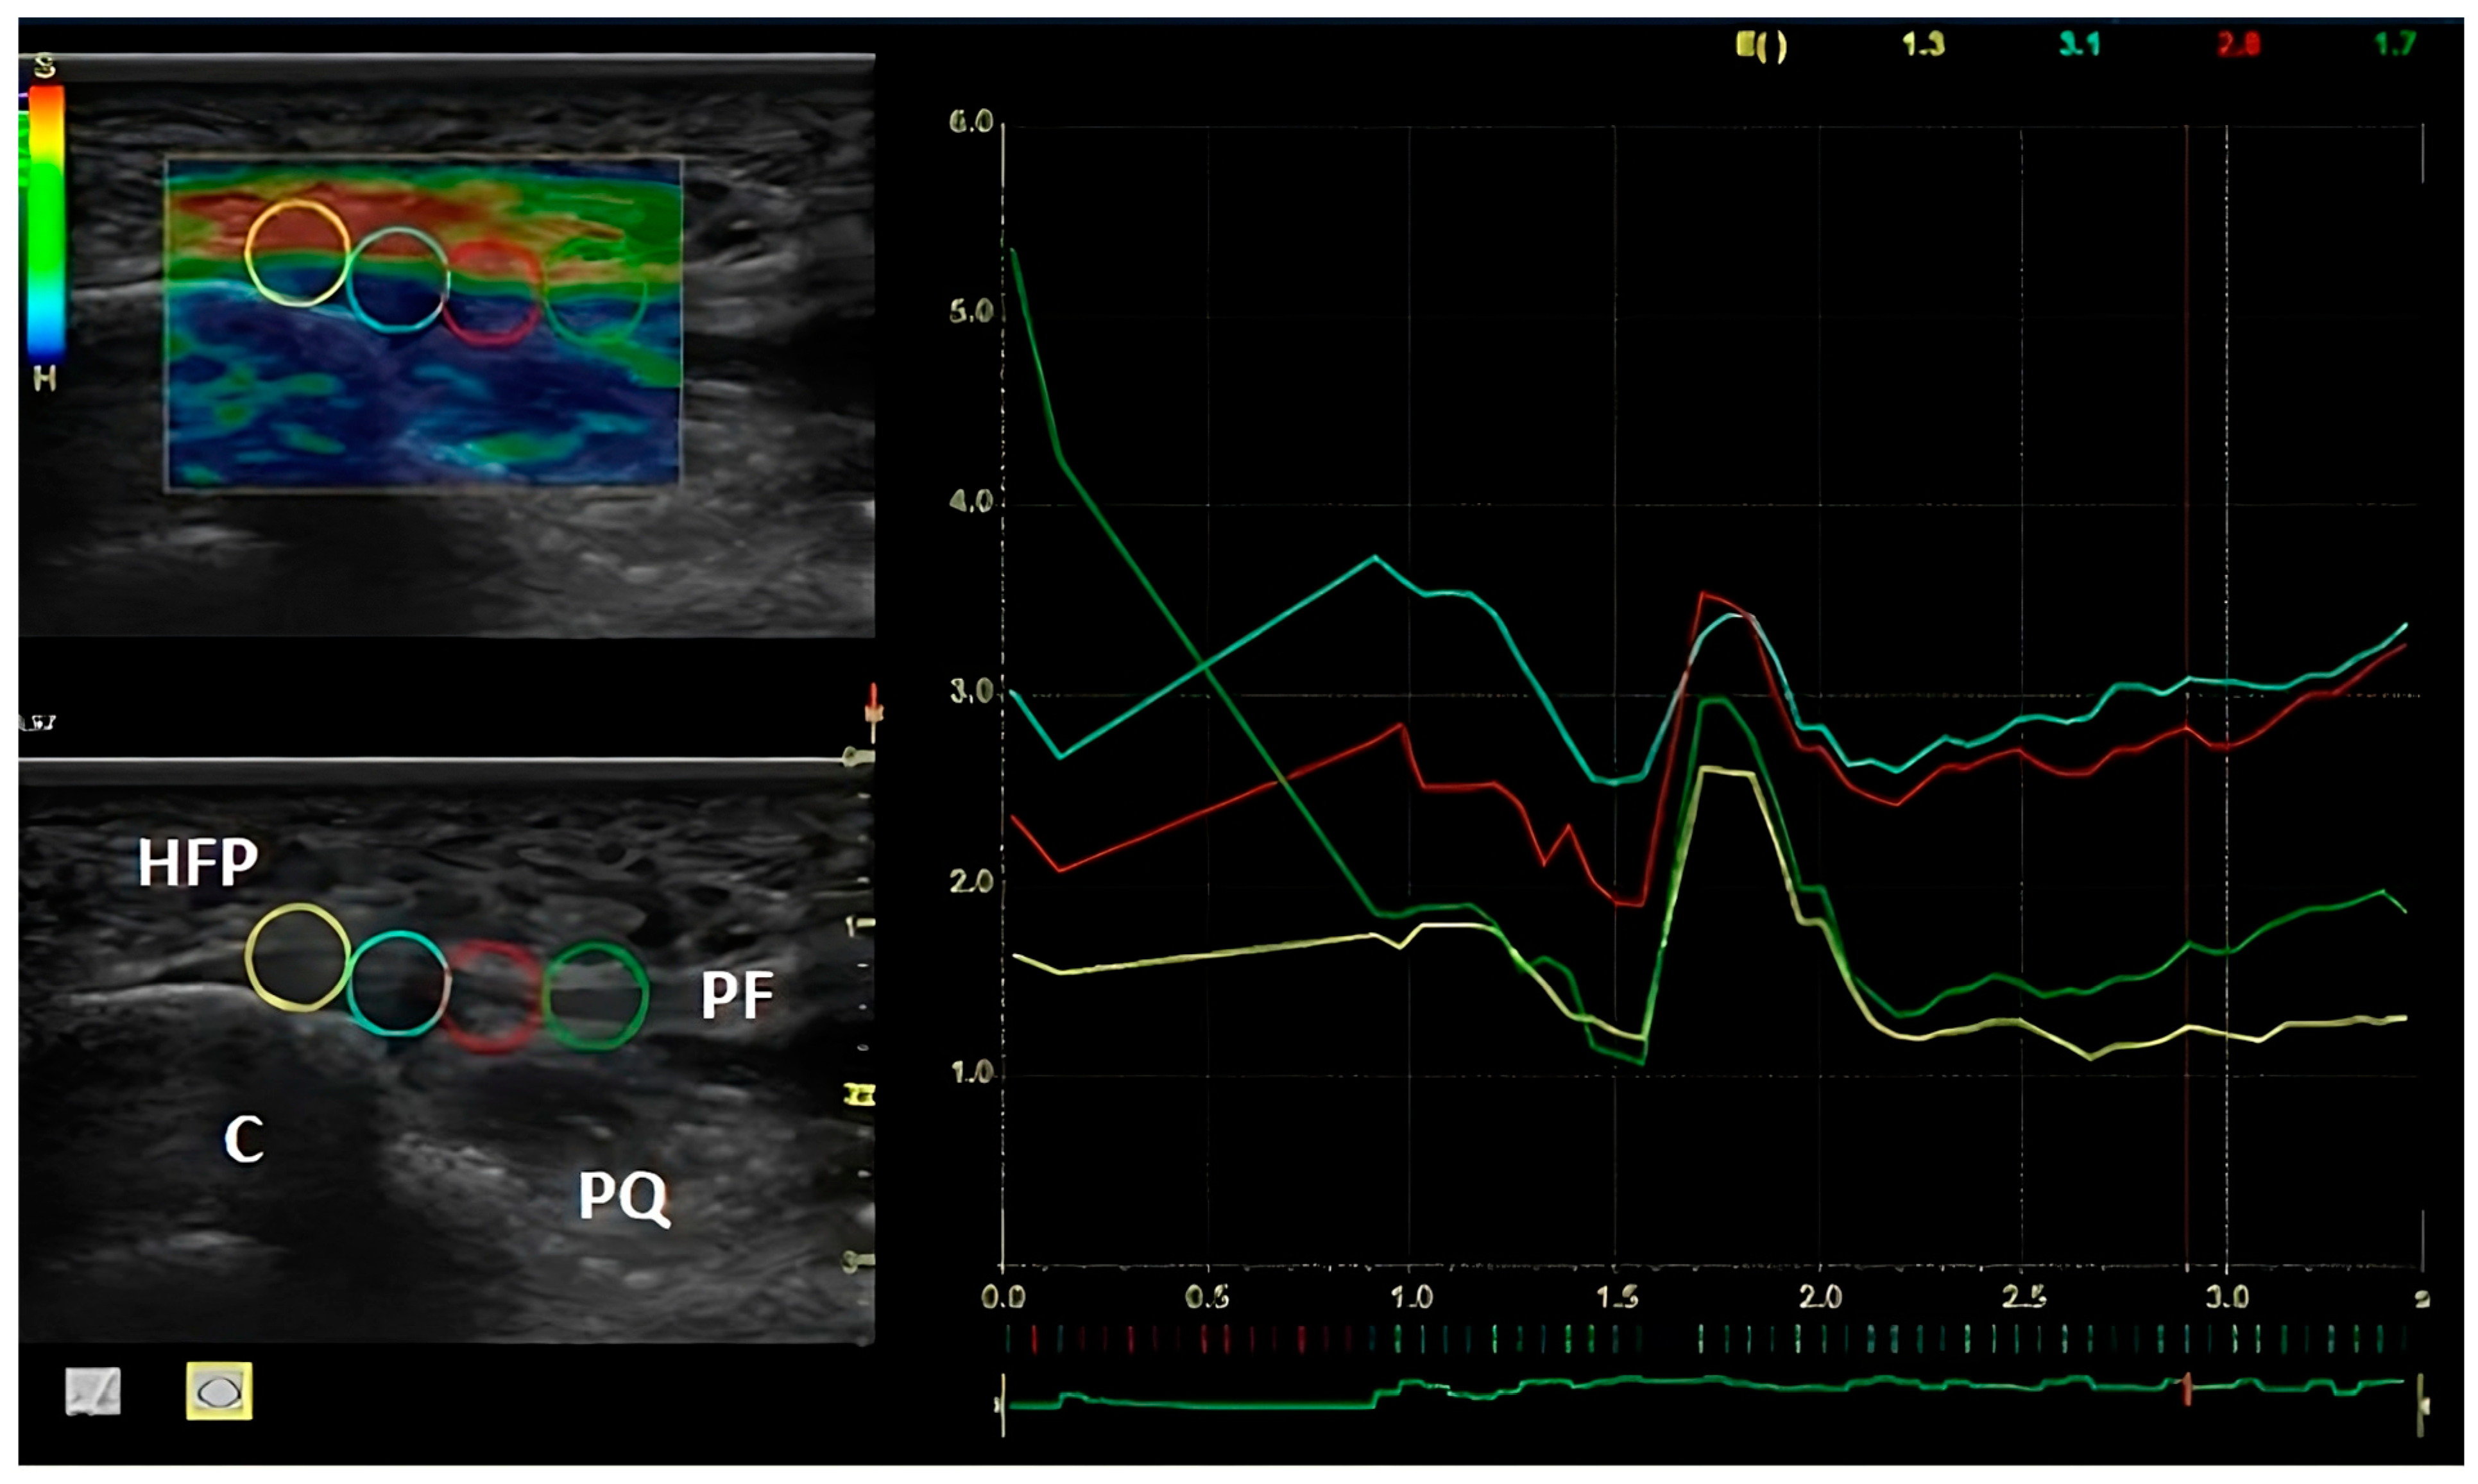

2.4. Procedures